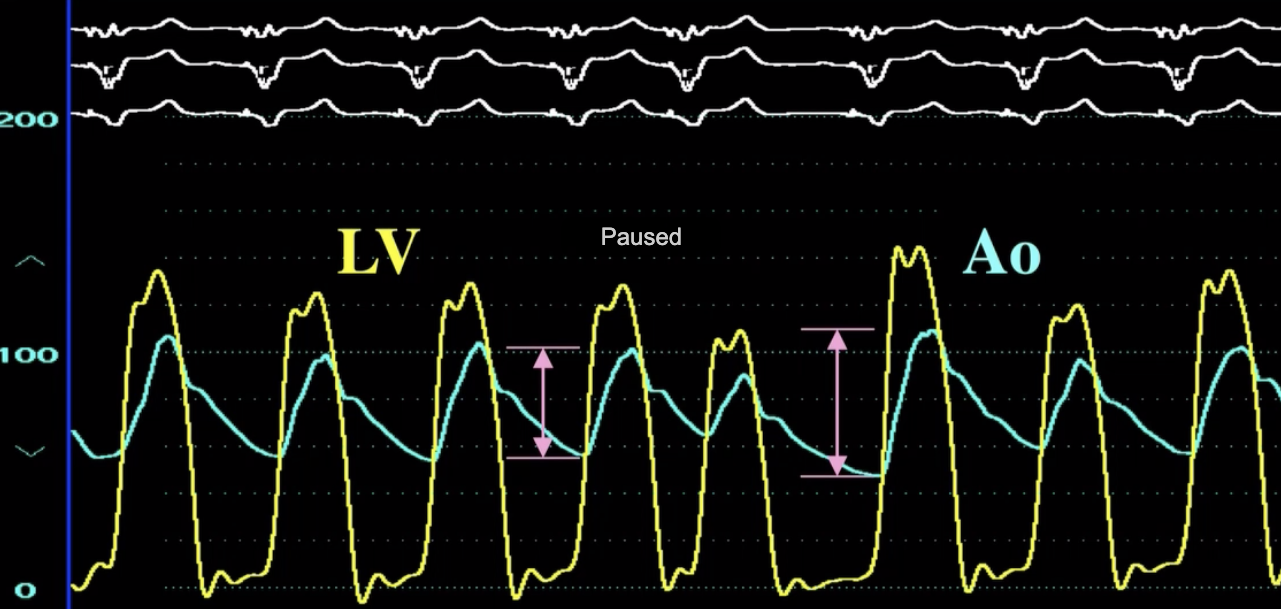

Describe the findings

AS